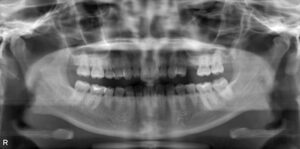

上顎3本欠損症例

BEFORE AFTER 73歳女性/上3本欠損/インプラント埋込手術 【治療内容】 右上の痛みが主訴でご来院の患者さん…